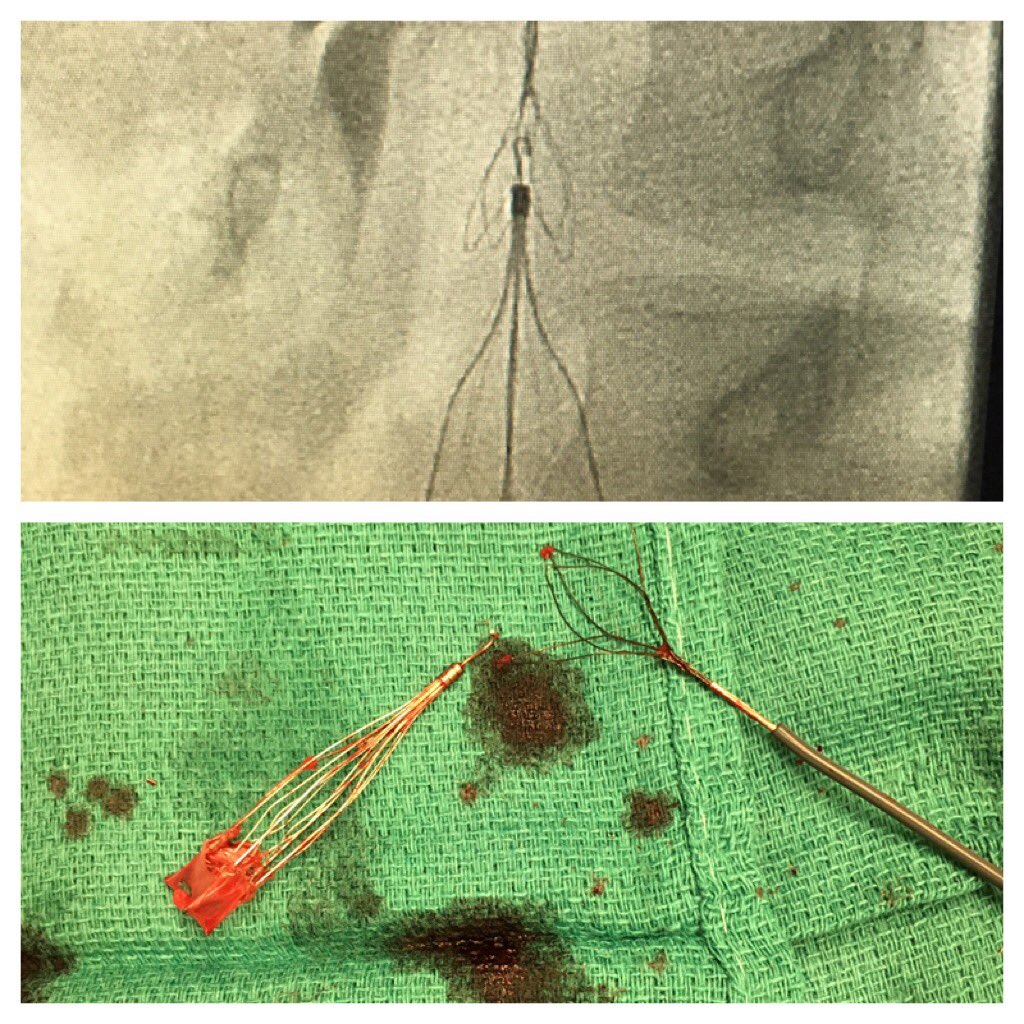

@AbhiKumar47

When the loop fails to engage...Clover snare kit + 💪🏻 #filterOUT. #GTFO #irad @CookMedical @SIRRFS @Drshiloh @SDhandMD @amdevane